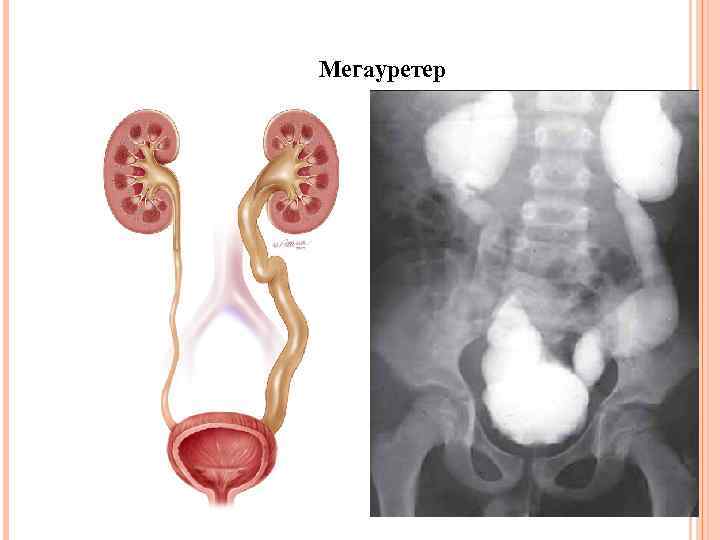

Мегауретер

Мегауретер